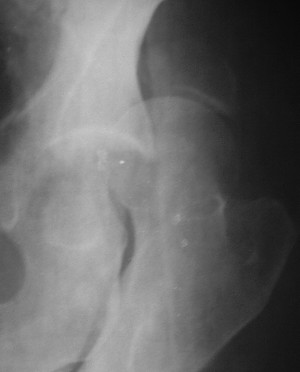

При поступлении в госпиталь 3.06.03

Больной 18 мая 2003 года в автоаварии получил перелом левой вертлужной впадины, вывих бедра. Госпитализирован в один из стационаров области.Вывих вправлен. В последствии бедро вывихивалось еще дважды. На консультацию был представлен снимок от 19.05.03г., больной переведен к нам 3.06.03г. Снимок при поступлении - перелом впадины, задне-верхний вывих бедра. 05.06.2003 г. выполнено открытое вправление вывиха левого бедра и остеосинтез стенки вертлужной впадины двумя винтами. Послеоперационный период без осложнений. Объем движений в левом тазобедренном суставе восстановился полностью. Выписан на амбулаторное лечение в удовлетворительном состоянии с рекомендациями 3 месяца ходить на костылях без нагрузки на оперированную конечность. На контрольных рентгенограммах левого тазобедренного сустава 13.10.2003 г. - признаки консолидации перелома; плотность, форма головки и состояние суставных поверхностей удовлетворительные. Разрешена дозированная осевая нагрузка, на конечность с использованием дополнительной опоры. 19.12.2003 г. больной обратился с жалобами на боли в левом тазобедренном суставе. На рентгенограммах левого тазобедренного сустава 19.12.2003 г., 20.02.04г. - асептичекий некроз головки бедра. 5.04.04г. - эндопротез. Сейчас ходит без трости, не хромает. Особенность эндопротезирования - при удалении винтов прослежена линия перелома заднего края впадины и предложено установить чашку несколько меньшего диаметра, чтобы она была покрыта несломанной частью.